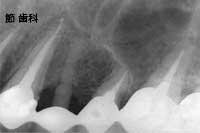

⑤ こちらは、左上の4〜6番目の3本の歯の連続した中間欠損で、同部分にU字型の“人工サファイヤ”タイプのインプラントを施し、前後の歯とブリッジ状に連結する事で欠損補綴を行ったものです。やはり、インプラントの底部が上顎洞底線にタッチするように埋入処置が行われていることが確認できます。